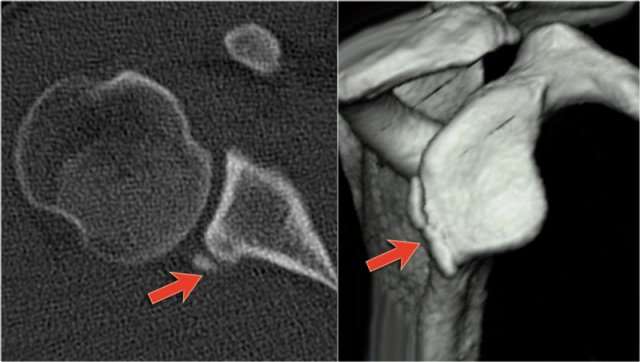

Osseus Bankart

Bankart lesions with an osseus fragment are common findings in patients with an anterior dislocation and are frequently seen on the x-rays or CT-scan.

On CT it is easy to appreciate the osseus fragment of the anterior glenoid (arrow).